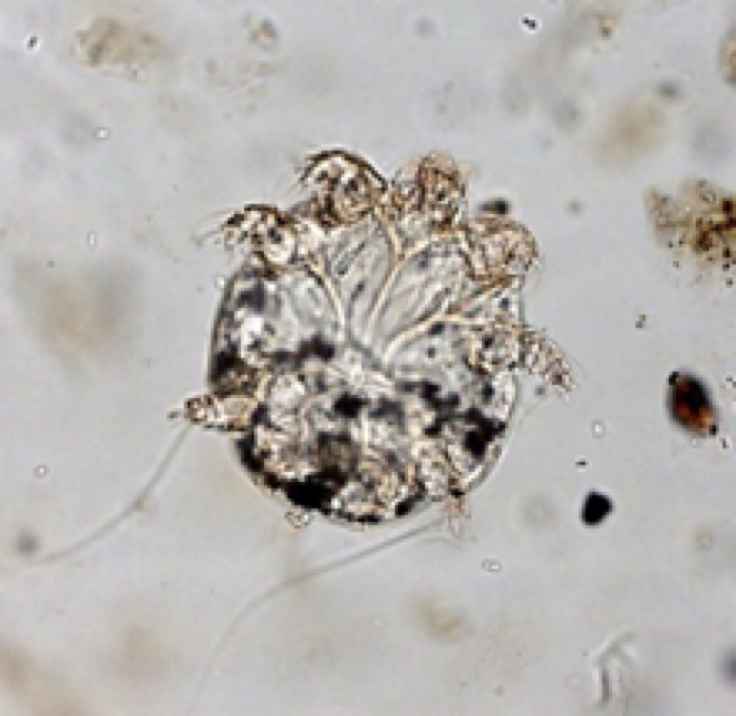

sarcoptes scabei

notoedres cati